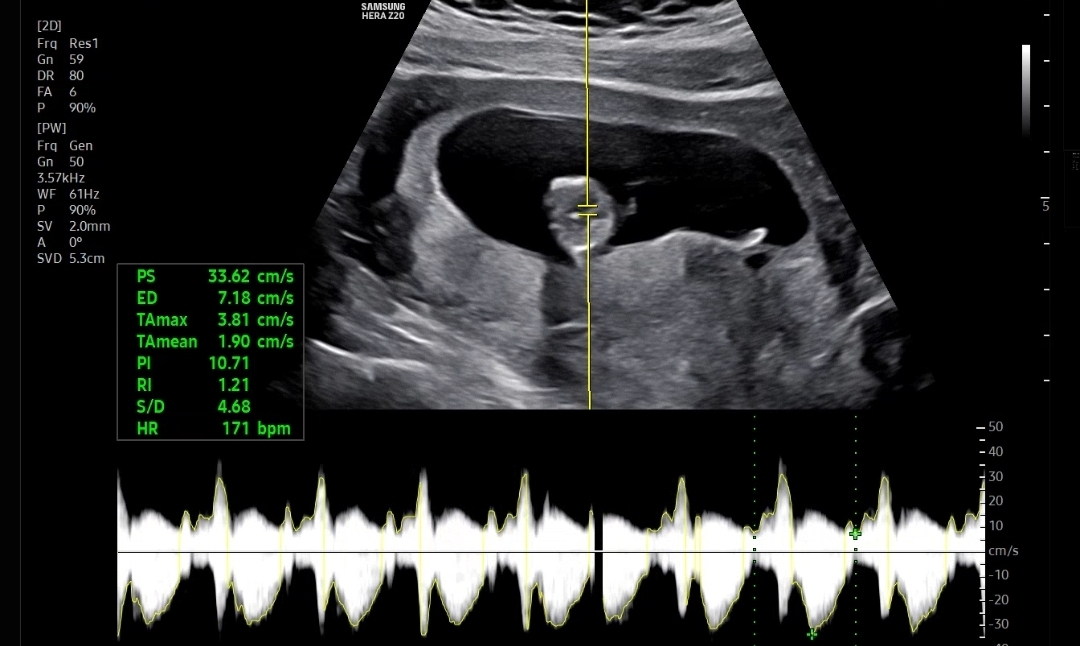

우선 아기크기와 심장소리를 확인했는데 아기크기도 6.26cm, 심장소리도 171bpm으로 잘 뛰고 있었다